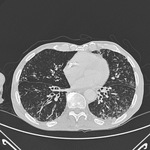

Chest CT with dilated and thickened airways and peripheral tree-in-bud pattern in a patient with bronchiectasis

From the personal collection of Dr S.M. Bhorade, University of Chicago Medical Center; used with permission